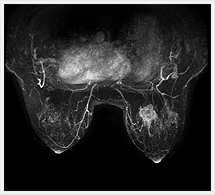

画像紹介

脳血管障害

乳房

MRIは他のモダリティに比べて乳管内癌の検出に優れ、乳癌の治療に際して広がり診断や多発などの存在診断に有用です。

造影剤を急速静注しながら連続撮影するダイナミック撮像が特に有用で、得られた画像から腫瘍のダイナミックカーブを作成します。これによって腫瘍の進展範囲の把握や良性悪性の質的診断を行っています。